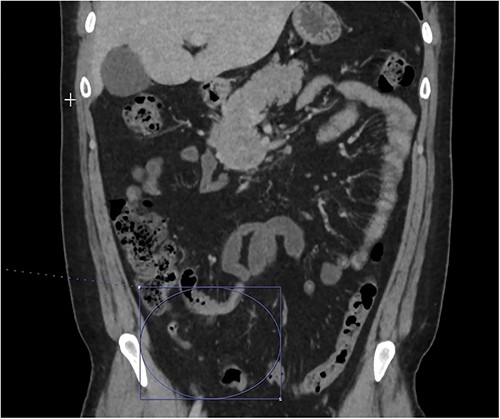

On presentation to the emergency department (ED), he was afebrile and normotensive with blood pressure in the 120s/80s though he had sinus tachycardia (heart rate 120–130 s). His abdomen was soft and diffusely tender with point tenderness at McBurney’s point and negative Rovsing’s sign. He had no signs of frank peritonitis. His complete blood count revealed leukocytosis (WBC 11K/μl), lactic acidosis (lactate 3 mmol/l), and mild transaminitis with AST 72 and ALT 101. An intravenous (IV) contrast-enhanced computed tomography scan of the abdomen/pelvis demonstrated a mildly dilated appendix (~8 mm) with surrounding fat stranding but no appendicolith, perforation, or abscess (Fig. 1). Interestingly, a partial portal vein (PV) and superior mesenteric vein (SMV) thrombosis were also noted (Fig. 2). Initial blood cultures were collected, which remained without growth.

Thrombosis can be seen extending into the mesenteric venous system as well as the intrahepatic portal veins; associated mesenteritis and abdominal ascites (not well visualized) are also seen.

Patient was admitted to the surgical service and started on broad-spectrum IV antibiotics (piperacillin–tazobactam) and was made nil per os. He was resuscitated intravenously with 2 l of crystalloid. Given the thrombosis of his PV and SMV, the patient was initiated on systemic anticoagulation with IV heparin which achieved therapeutic dosing within 24 hours. Over the course of the next few days, his abdominal pain and tachycardia improved. Interval CT abdomen/pelvis scan 5 days from presentation demonstrated progression of the thrombus to involve lobar, segmental, and subsegmental portal venous branches as well as the splenic vein distal to the portosplenic confluence (Fig. 2).